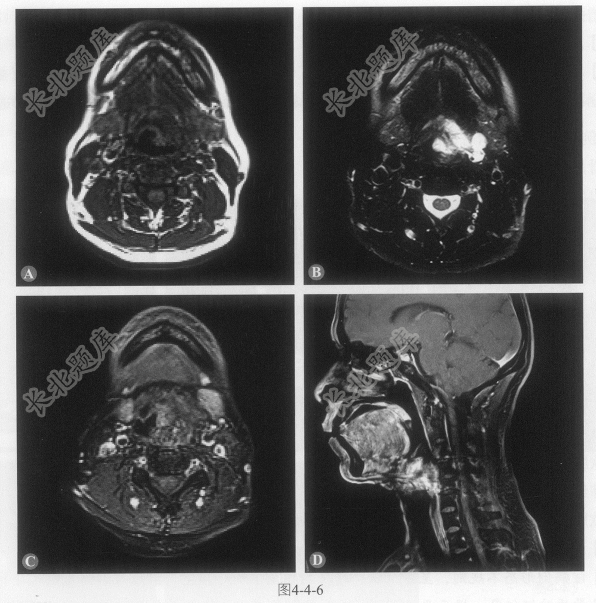

患者男性,54岁,因咽痛、呛咳1月余,声嘶3天就诊。MRI检查如图4-4-6。

- 多项选择题1.在提供的MRI图像上,病灶可能累及的部位有:

A、会厌前间隙

B、下咽左侧壁

C、左侧杓状软骨

D、咽后壁

- 多项选择题2.在提供的MRI图像上,关于病灶征象描述正确的是:

A、病灶呈等T

、长T2信号B、病灶匍匐生长,与邻近组织分界不清

C、增强扫描实质部分明显强化

D、T2WI可见点状、条状血管流空影

- 多项选择题3.该病例最有可能诊断为:

A、下咽血管瘤

B、下咽淋巴瘤

C、下咽慢性脓肿

D、下咽神经鞘瘤